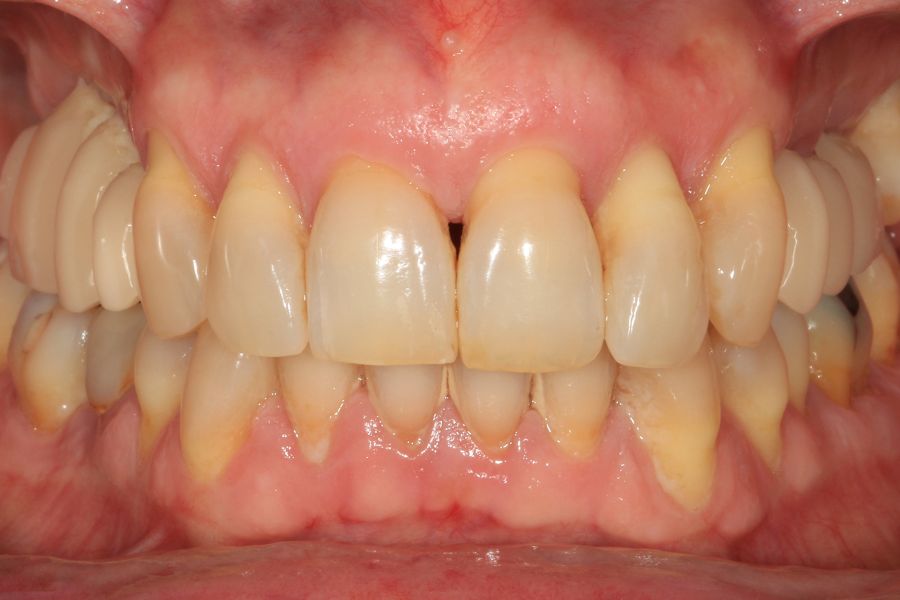

Presentamos el caso de una paciente femenina de 56 años de edad que acude a la consulta demandando un tratamiento con implantes dentales para reponer los dientes ausentes en ambos sectores posteriores maxilares. En ambos cuadrantes superiores, los molares se perdieron hace varios años. La paciente no se ha realizado la reposición de los mismos hasta ahora, ya que en otros centros consultados la propuesta terapéutica fue la de realizar injertos y regeneración ósea para poder ganar volumen óseo suficiente antes de colocar los implantes. La paciente busca otras alternativas menos invasivas y por ello acude a la visita. En las imágenes intraorales se observa la falta de los molares en los sectores posteriores maxilares con excepción del 27, que actualmente tiene un compromiso periodontal importante (Figuras 1-4). El resto de dientes también se encuentran afectados por una enfermedad periodontal avanzada con pérdida ósea horizontal (Figura 5).